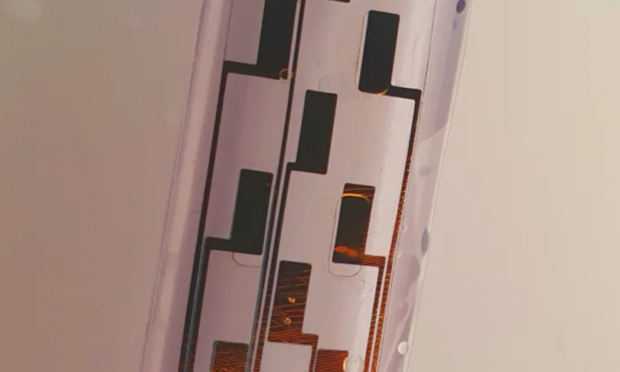

Η συσκευή, την οποία δημιούργησαν ερευνητές του Πανεπιστημίου του Κέιμπριτζ, που έκαναν τη σχετική δημοσίευση στο περιοδικό «Science Advances», μπορεί να τυλιχθεί μέσα σε έναν μικροσκοπικό κύλινδρο, να τοποθετηθεί σε μία βελόνα και να εμφυτευθεί στη σπονδυλική στήλη (στην περιοχή όπου γίνονται οι επισκληρίδιες ενέσεις για να ελεγχθούν οι πόνοι του τοκετού), χωρίς να χρειαστεί επεμβατική διαδικασία.

Όταν βρεθεί μέσα στο σώμα, η συσκευή φουσκώνει με νερό ή αέρα και ξετυλίγεται σαν ένα μικρό στρώμα που καλύπτει ένα μεγάλο τμήμα του νωτιαίου μυελού. Όταν συνδέεται με μία γεννήτρια παλμών, τα ηλεκτρόδια της συσκευής αρχίζουν να στέλνουν ηλεκτρικά σήματα στον νωτιαίο μυελό, μπλοκάροντας τα σήματα του πόνου.

Οι έως τώρα συσκευές μπλοκαρίσματος του νωτιαίου μυελού κατά του πόνου είναι ογκώδεις και απαιτούν επεμβατικό χειρουργείο, γι’ αυτό μόνο 50.000 τέτοιες επεμβάσεις γίνονται κάθε χρόνο παγκοσμίως (η σχετική θεραπεία θεωρείται ως μέτρο τελευταίας καταφυγής για όσους ασθενείς νιώθουν πολύ σοβαρούς και μη αντιμετωπίσιμους πόνους). Η νέα συσκευή είναι πολύ πιο μικρή σε μέγεθος (έχει πάχος μόλις 60 εκατομμυριοστά του μέτρου) και είναι πιο εύκολο να εισαχθεί στο σώμα.